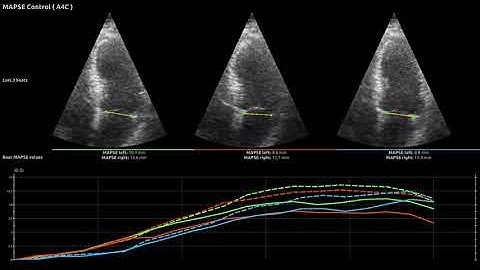

Left ventricular function - multimodality considerations & MAPSE, Prof Martin Ugander